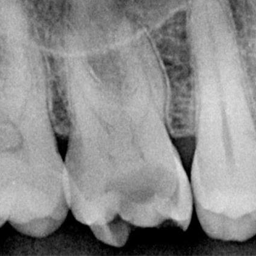

Нарийн оношилгоо

X-ray-ээр шүдний цоорхойн хүрээ болон гүнзгий байдлыг нарийн тодорхойлно.

Эмчилгээний төлөвлөгөө

Цоорсон шүдний шатанд тохирсон хамгийн сайн эмчилгээний аргыг тодорхойлох